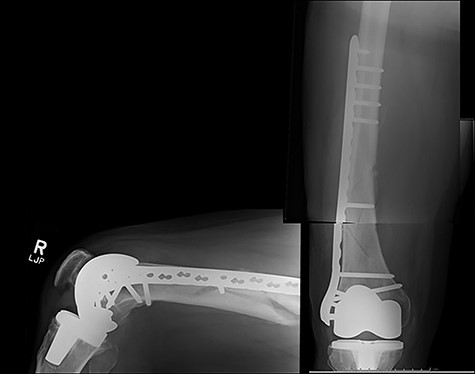

Case 4 (Figs 8–10): once again, screw placement too close to the fracture site has resulted in internal plate stresses exceeding its load-bearing capacity.

Inter-fragmentary screws have been utilized here. This lady may have benefited from placing an anterior bridging plate at the time of her original procedure if it was not possible to avoid this screw configuration.